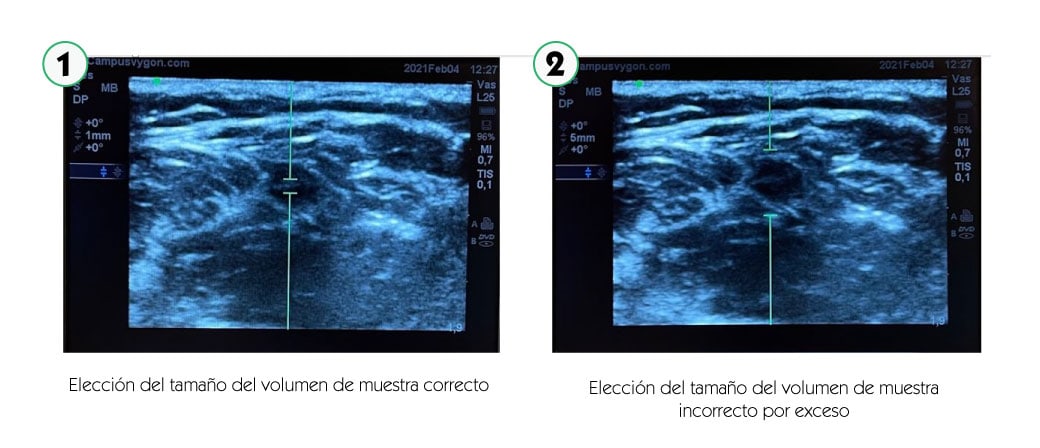

Manteniendo la exploración en modo B, activamos el modo doppler espectral. A continuación, colocamos el volumen de muestra (identificado como dos líneas paralelas y perpendiculares al eje del haz de ultrasonidos) en el interior del vaso que se pretende estudiar. El tamaño del volumen de muestra debe ser proporcional al calibre del vaso a estudiar.